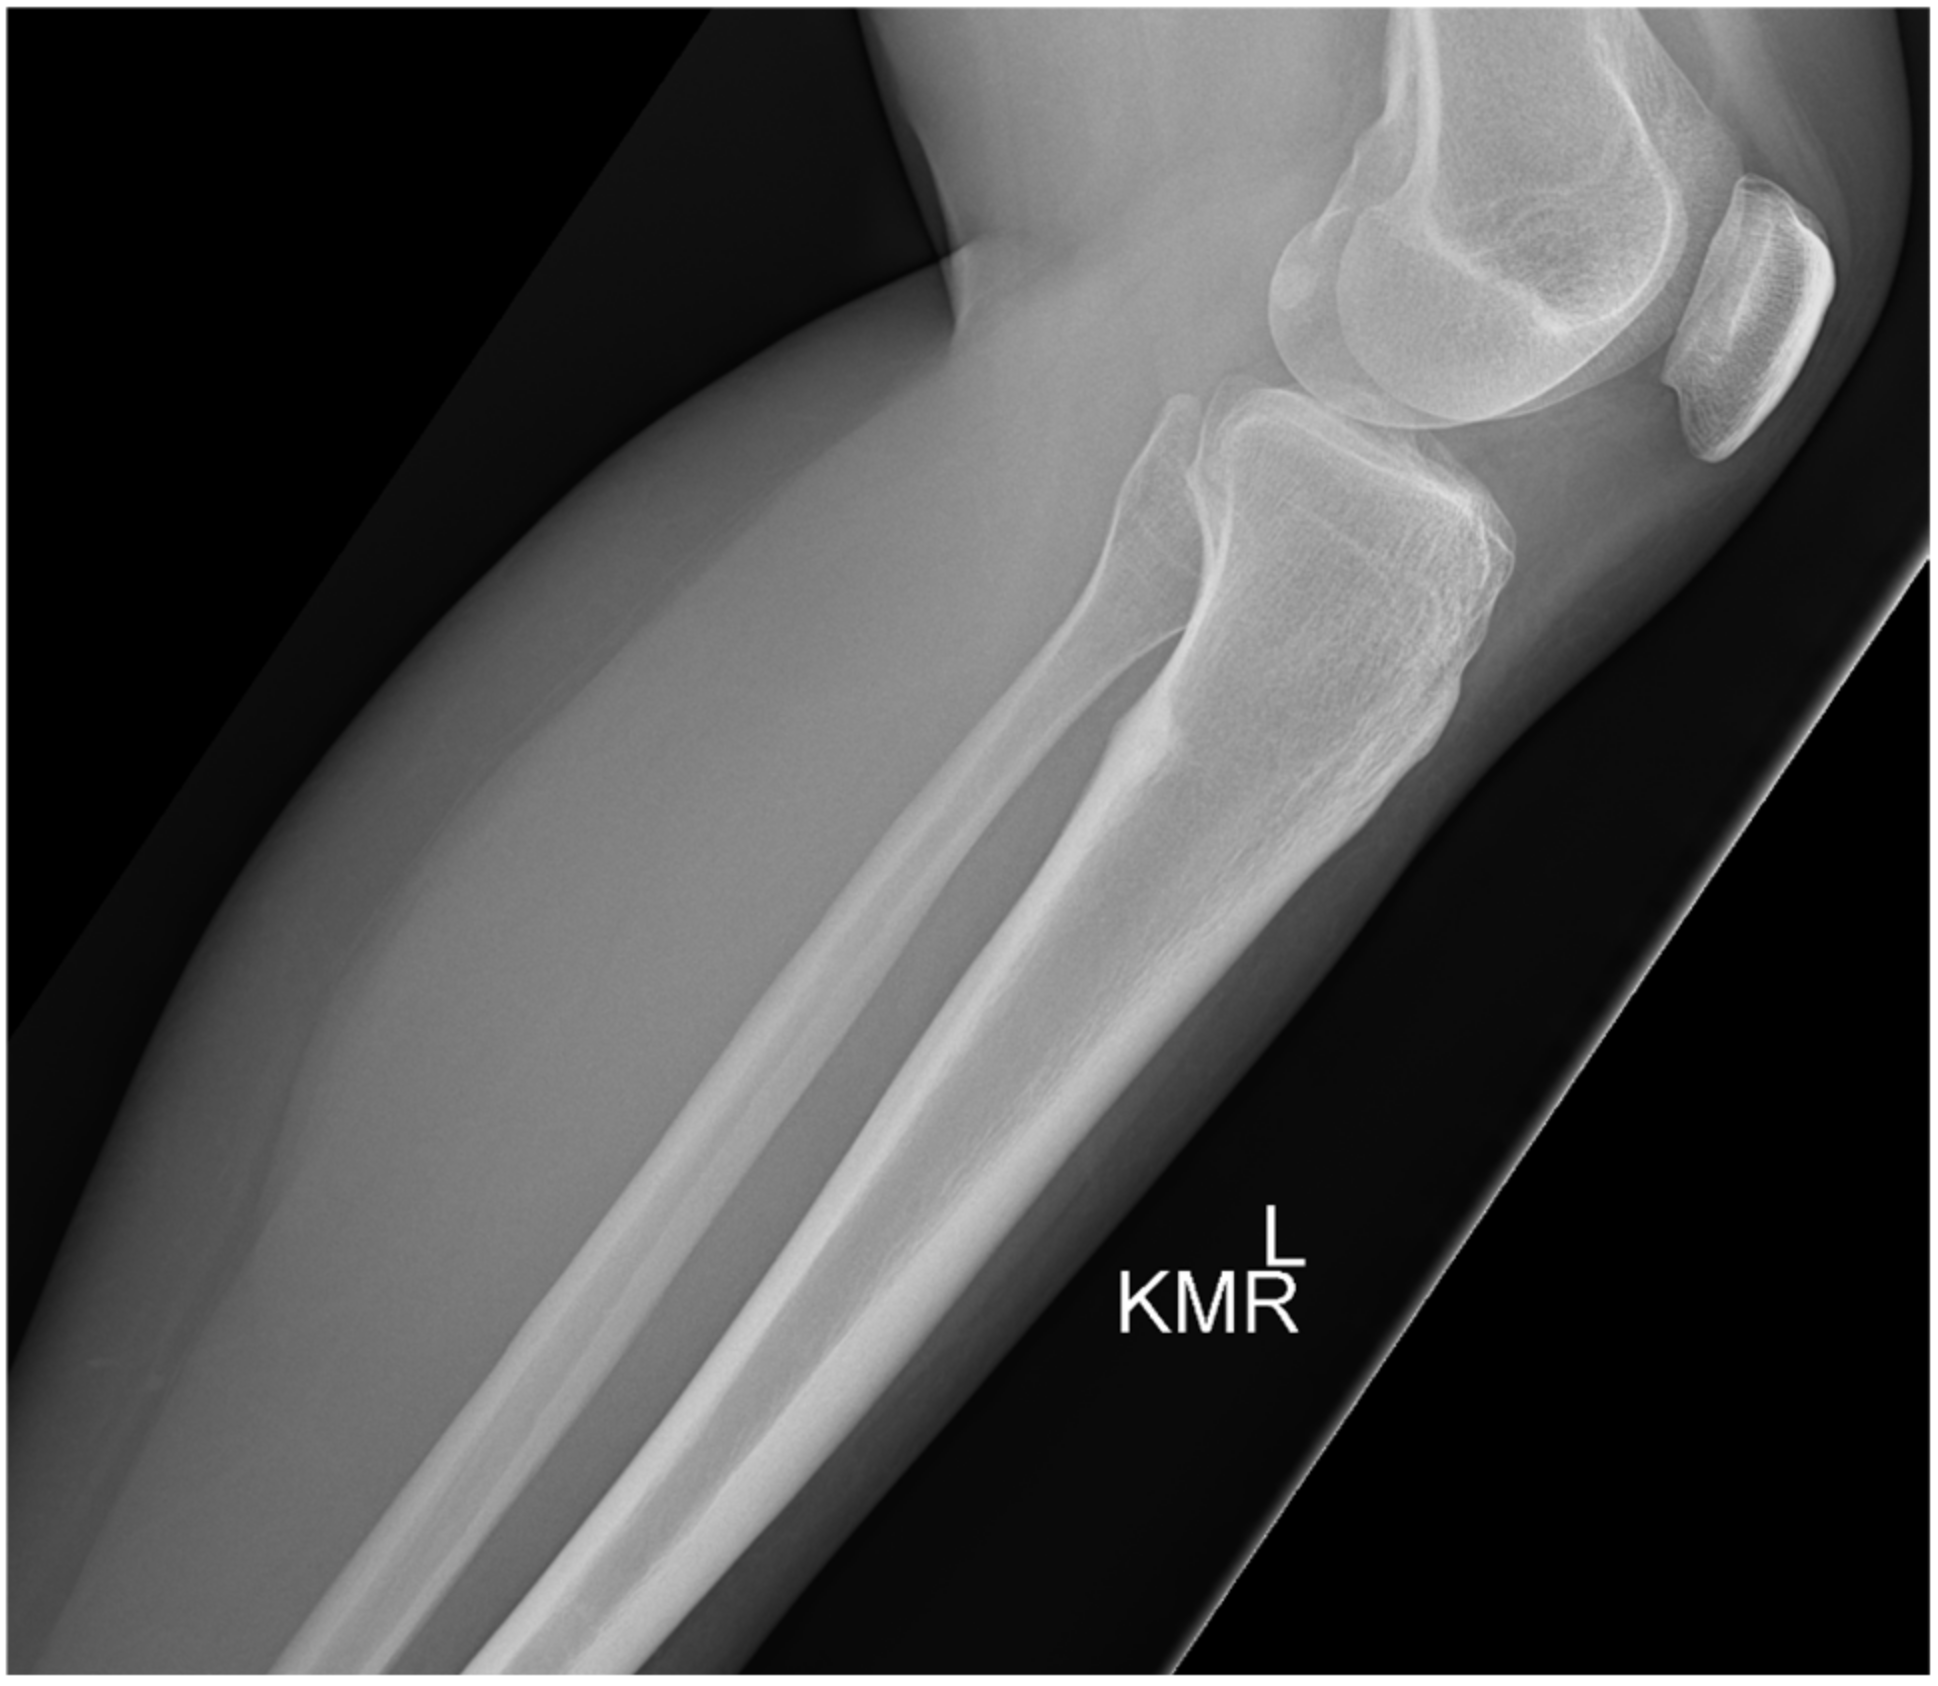

2. Case 1